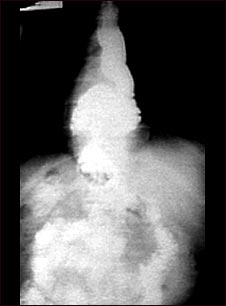

Radiografía de una hernia hiatal

Esta radiografía muestra una protrusión, a través del diafragma, de la porción superior del estómago (hernia hiatal).